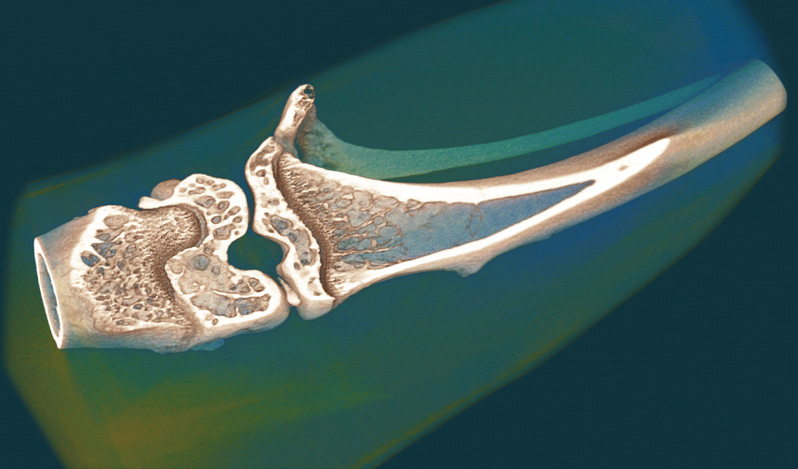

小鼠股骨体积渲染3D模型